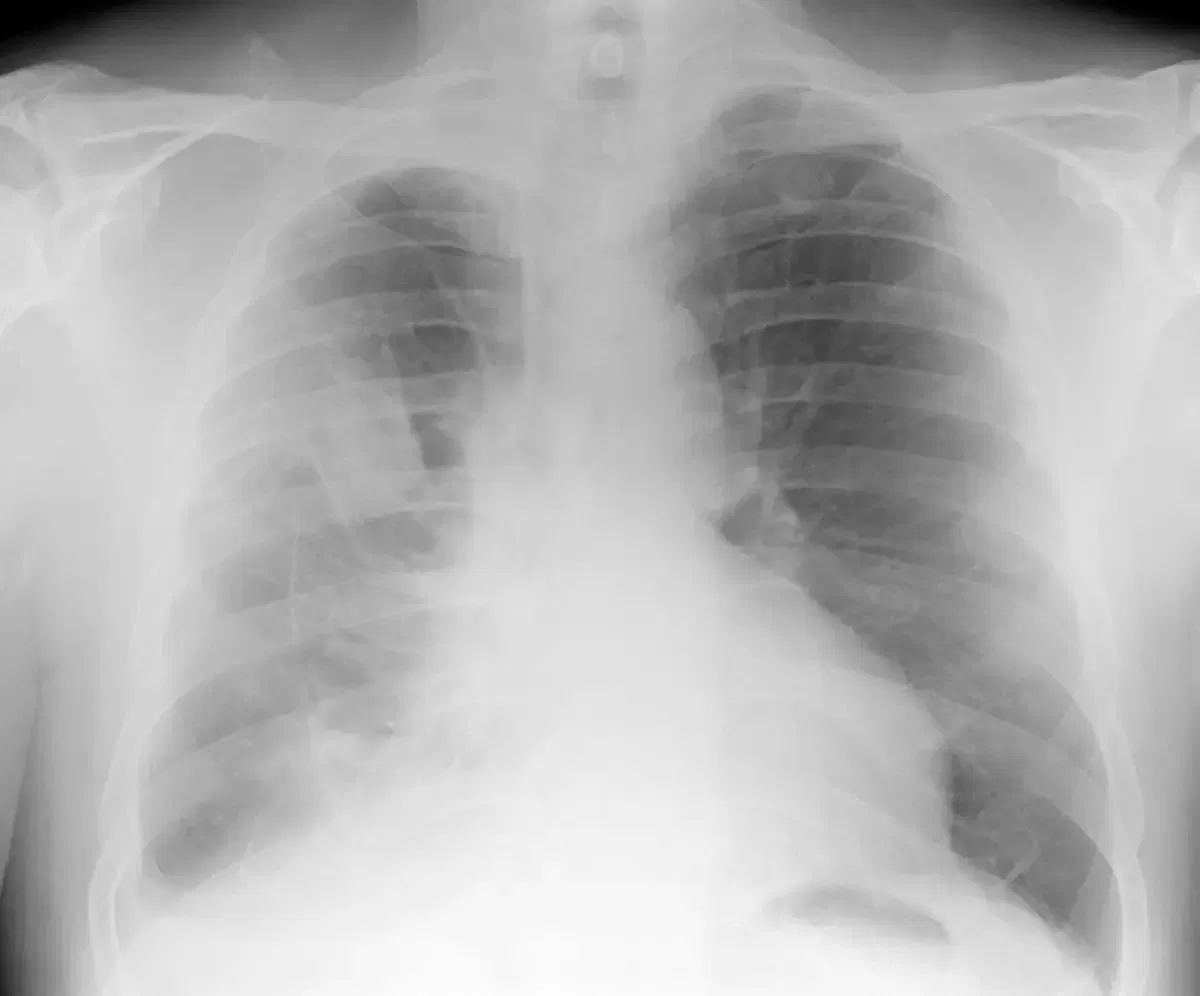

If this occurs in the pleura (pleural mesothelioma), fluid builds up in the lungs causing pleural effusion, and the lungs no longer function normally. Fluid will need to be drained periodically. Similarly, fluid can build up in the sac that surrounds the heart, causing pericardial effusion.

The GP will likely organise Xray's and/or a CT scan and blood tests. If there is a collection of fluid, further investigation may be required and drainage of the fluid carried out where a sample of fluid is sent to pathology for testing.

Sometimes a diagnosis is not able to be made from the pleural fluid. In this case a cardiothoracic surgeon will perform a pleural biopsy where a sample is taken and examined under a microscope.